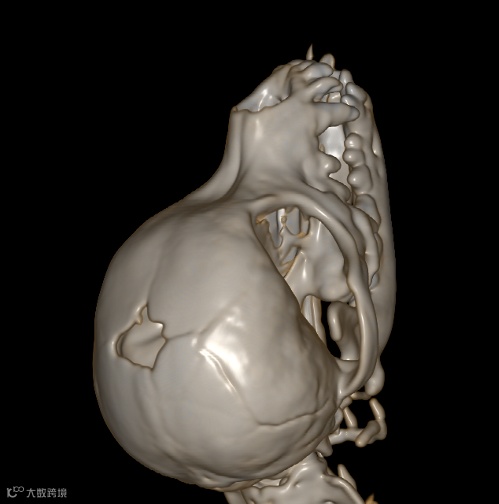

| 右侧眼眶壁内前侧骨折 |

| 右侧顶骨及颞骨骨折 |

| 大脑右侧顶部脑挫裂伤 |

| 先天性脑囟门未闭合;右侧耳道少许积液 |

1、右侧眼眶壁骨折

2、右侧顶骨及颞骨骨折伴周围软组织稍肿胀

3、大脑右侧顶部脑挫裂伤

4、先天性脑囟门未闭合

5、右侧耳道少许积液

余未见明显异常,请结合临床。